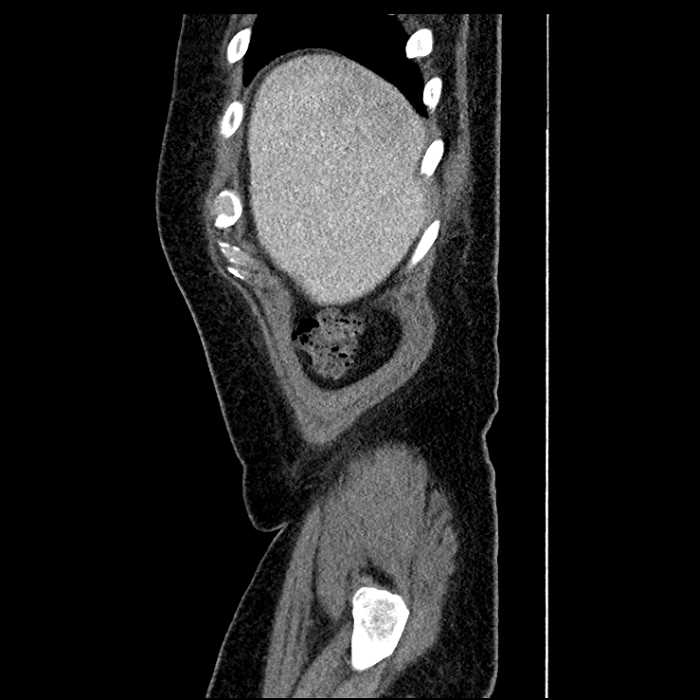

• Mild mural thickening of a segment of the sigmoid colon with adjacent fat stranding and a 1.5 cm fluid and gas collection along the tip of an inflamed diverticulum

• Loss of the normal fat plane between this collection and adjacent loops of small bowel, which demonstrate mural thickening

Acute sigmoid diverticulitis complicated by a small contained perforation and a large abscess in the right hepatic lobe. Additional small subcapsular abscesses along the anterior margin of the left hepatic lobe.

Additionally, loss of the normal fat plane between the peridiverticular collection and adjacent thickened loops of small bowel raises the potential for an enterocolonic fistula.

Hepatic abscess showing the double target sign with low density internally surrounded by a thin inner enhancing rim (red arrow) and ill-defined outer low density rim (yellow arrow). Blue arrow indicates an internal septation. Red arrows: additional smaller subcapsular abscesses. Red arrow: focal contained perforation associated with diverticulitis.